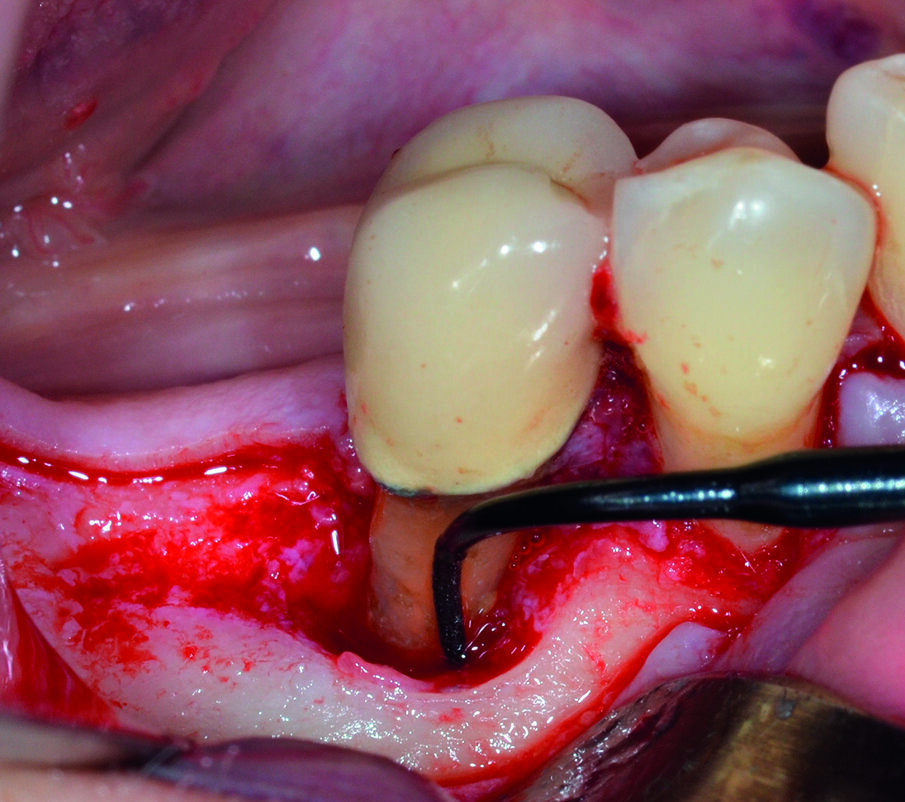

Dopo analgesia locale ottenuta per infiltrazione di Articaina cloridrato 40 mg con epinefrina 1:100.000 viene effettuata l’ incisione di accesso in accordo con il protocollo chirurgico sopra citato (Fig. 4). Al sollevamento del lembo è possibile evidenziare un profondo difetto che coinvolge l’aspetto disto-buccale dell’ elemento 4.5; con una sonda parodontale millimetrata di tipo Williams viene misurata la profondità della componente intraossea (Figg. 5-7). Il debridement della lesione e la decontaminazione della superficie radicolare vengono effettuati mediante una coppia di inserti dedicati montati su dispositivo ad ultrasuoni (ES030LDT ed ES030RDT, Esacrom Srl, Imola, Italia) (Fig. 8).

La particolarità di questi inserti è quella di avere una curvatura orientata verso destra (ES030RDT) e verso sinistra (ES030LDT): in tal modo, risulta molto più agevole operare sul versante buccale o linguale/palatale a seconda dei casi (Figg. 9, 10). Grazie all’effetto combinato della cavitazione ultrasonica e del microstreaming acustico vengono effettuati sia la rimozione del tessuto reattivo che la completa decontaminazione della superficie radicolare (Fig. 11). Al termine del trattamento con ultrasuoni, è possibile valutare l’aspetto intraoperatorio dell’area interessata dal difetto (Fig. 12).

Considerata l’estensione e la profondità del difetto intraosseo, viene selezionata una membrana in corticale di origine eterologa in virtù della sua intrinseca stabilità dimensionale e della maggior resistenza alla degradazione rispetto a una membrana riassorbibile in collagene: dal punto di vista chirurgico, è di fondamentale importanza che la membrana stessa sia correttamente sagomata e fissata in maniera sufficientemente stabile sia lingualmente che buccalmente (Fig. 13).